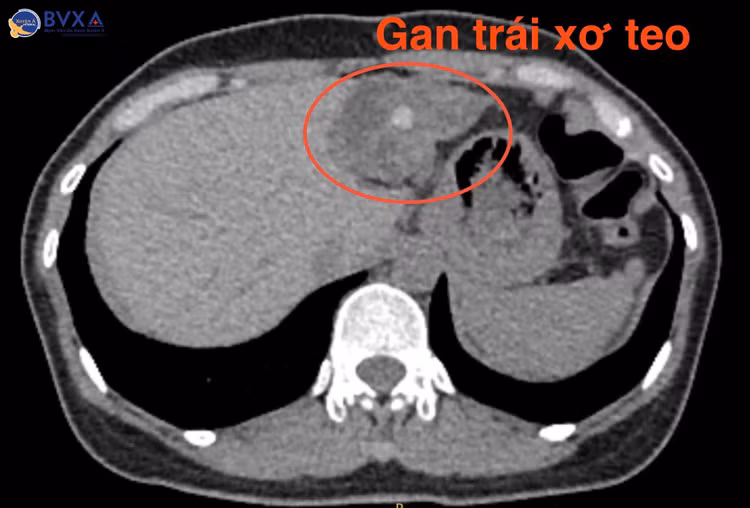

Tại đây, qua thăm khám kỹ lưỡng và thực hiện các cận lâm sàng chuyên sâu như chụp CT-scan bụng, kết quả cho thấy bệnh nhân có nhiều sỏi đường mật trong gan trái và sỏi túi mật, cùng với đó là gan trái bị xơ teo nhỏ.

Dựa trên các kết quả chẩn đoán hình ảnh, bác sĩ nhận định sỏi đã hình thành lâu trong ống mật chủ dẫn đến tắc mật, đồng thời ống gan trái bị chít hẹp khiến cho toàn bộ thùy gan trái của bệnh nhân đã bị xơ teo và tạo các túi sỏi.

Với triệu chứng đau bụng tái diễn nhiều lần, gây ảnh hưởng không nhỏ đến sinh hoạt hàng ngày nên chị H.T.K.H., (47 tuổi, ngụ Sóc Trăng) đã tìm đến Bệnh viện Đa khoa Xuyên Á Vĩnh Long để thăm khám, phát hiện bị sỏi lấp đầy ống mật chủ và gan trái, khiến cho chị bị xơ teo gan trái.

Gan trái xơ teo vì sỏi - Ảnh BVCC